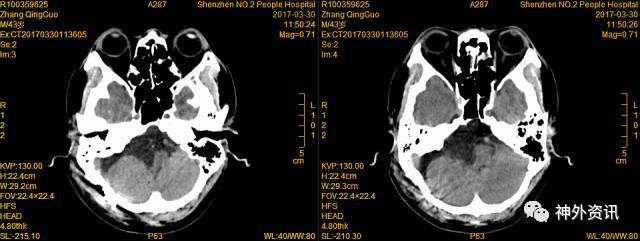

术后72小时CT

术后14天复查CT